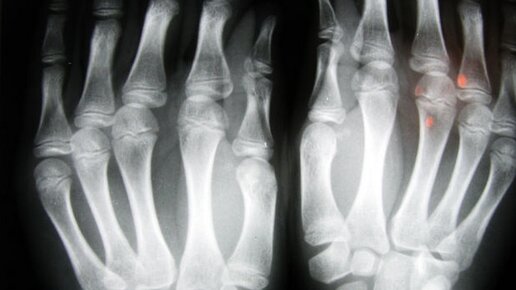

Как отличить ушиб пальца от перелома?

Одними из наиболее частых травм считаются переломы и ушибы пальцев. Открытый перелом или перелом со смещением, конечно же, ни с чем невозможно перепутать. И в этом случае необходимо придать костям правильное положение, зафиксировать, обработать открытую рану и срочно обратиться за медпомощью. Но вот отличить сильный ушиб от перелома довольно сложно, поскольку болезненные ощущения на самом деле одинаковые. Причем некоторые переломы иногда практически даже не болят. Но есть определенные признаки, которые...